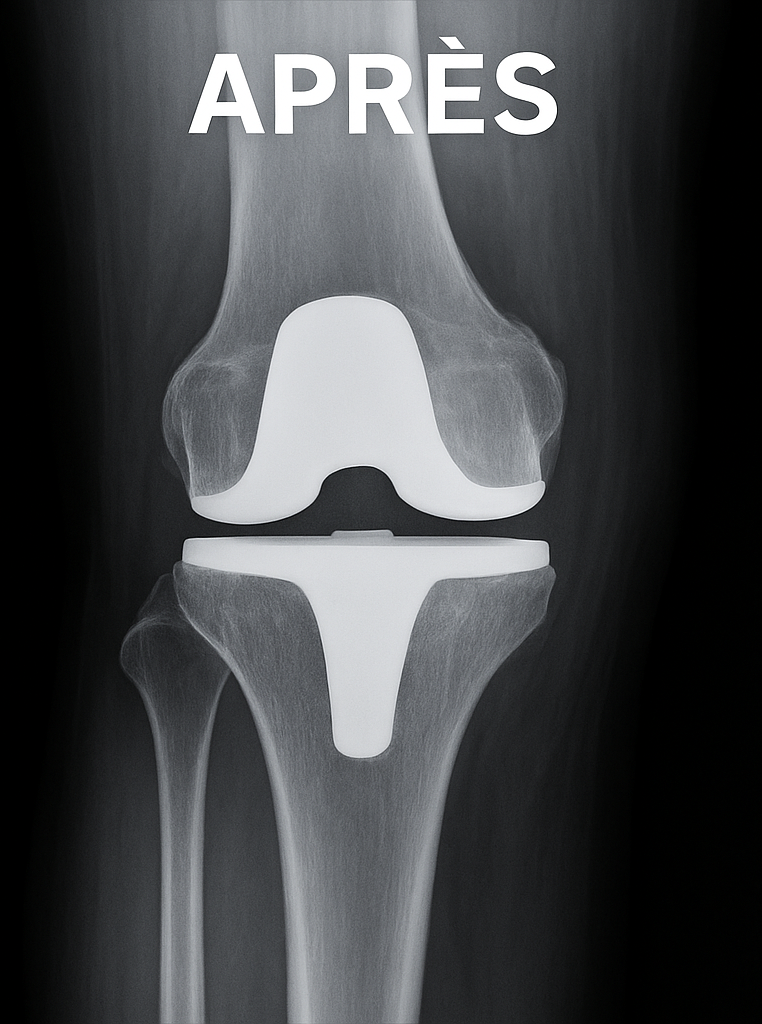

Illustration radiologique

Prothèse du genou